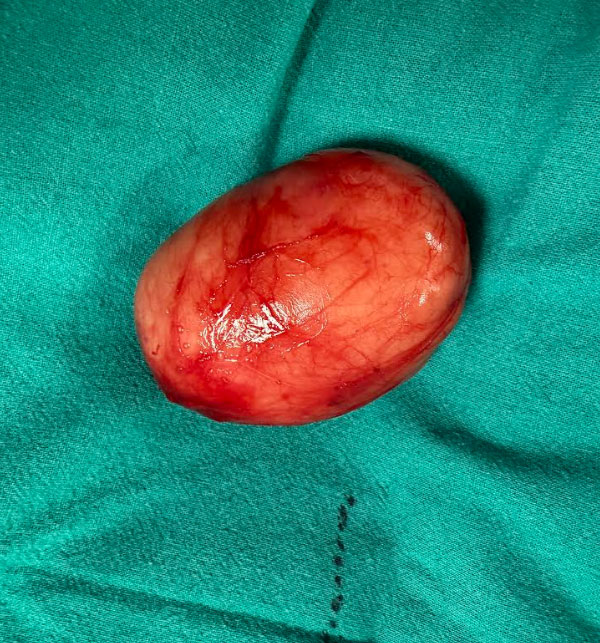

Given the size of the cyst and the proximity to vital structures, surgical intervention was necessary. The patient underwent a formal excision of the mass. The surgical objective was twofold: ensure the complete removal of the cyst wall to prevent recurrence, while meticulously preserving the adjacent neurovascular bundle – Mainly the Carotid Artery and the IX and XII Cranial nerves.

We are pleased to report that the surgery was successful, and the mass was excised in its entirety.

Outcome & Histopathology

The final histopathology report definitively confirmed the diagnosis: Branchial Cleft Cyst.